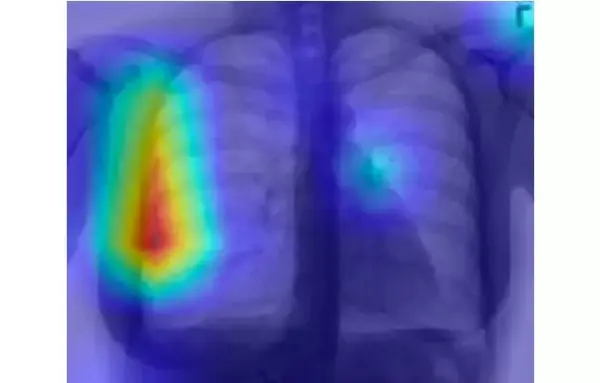

用 CAM 解释 CNN 的输出

CAM 是一种可视化图片在 CNN 中最后的卷积层上被「注意」区域的方法。请注意,CAM 可视化适用于在最终全连接层之前具有全局平均池化层的架构,其中我们输出最后一个卷积层上每个单元的特征映射的空间平均值。

在气胸分类器的背景下,这相当于强调胸透照片中识别(或未识别到)气胸最为重要的那些像素。

正如气胸阳性的胸透照片示例所展示的那样,CAM 最终可以可视化为一张热图。